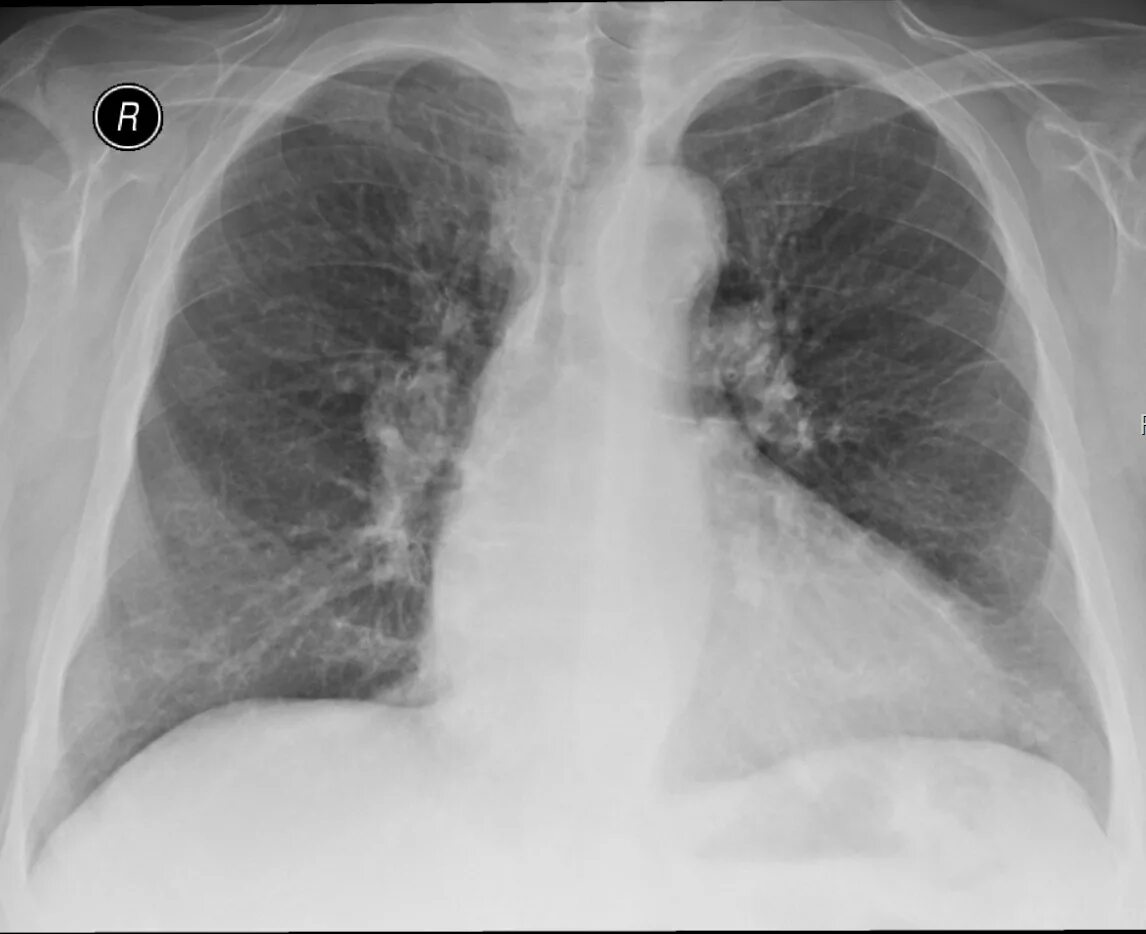

Обызвествление в проекции